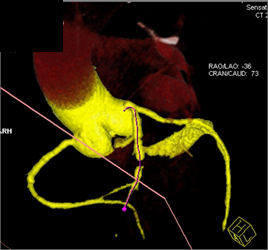

Diagnosis

Diseased LAD